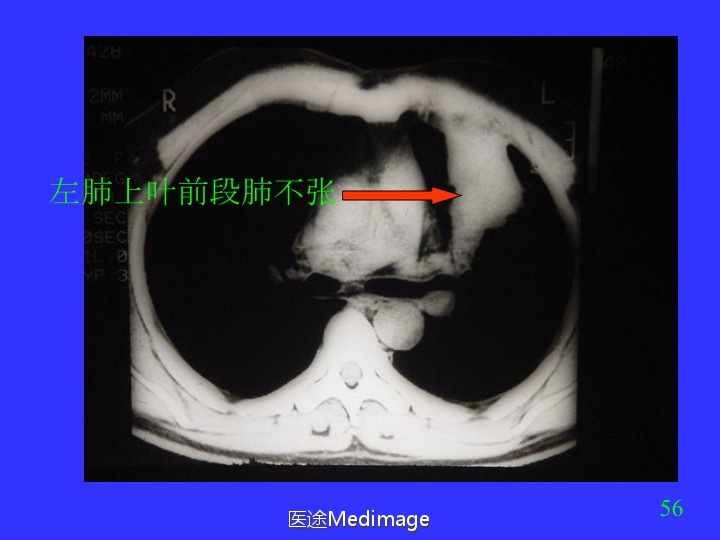

胸部CT阅读与诊断(三)各种肺不张